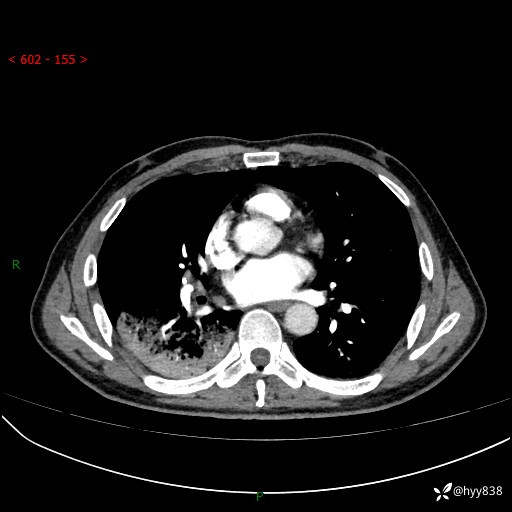

63岁/男,发热5余天。精彩好病例,“大叶性肺炎”,等你来诊---结果公布~

【患者信息】:63岁/男

【主诉】:发热5余天

【现病史及既往史】:患者5余天无明显诱因出现畏寒寒战发热,最高体温39.5℃,发热无明显昼夜规律,伴全身乏力、头晕,无头痛、无咳嗽咳痰、无胸痛咯血、无气短、无腹痛腹泻、无尿频尿急尿痛等不适,于当地市第五人民医院就诊,予以抗感染等治疗(具体不详)后发热无明显好转,1天前查胸部CT提示右下肺感染,为求进一步诊治,门诊以“社区获得性肺炎”收治入院; 起病以来,患者精神、食欲一般,睡眠可,大小便正常,体力体重较前无明显变化。

【检查】:胸部CT增强